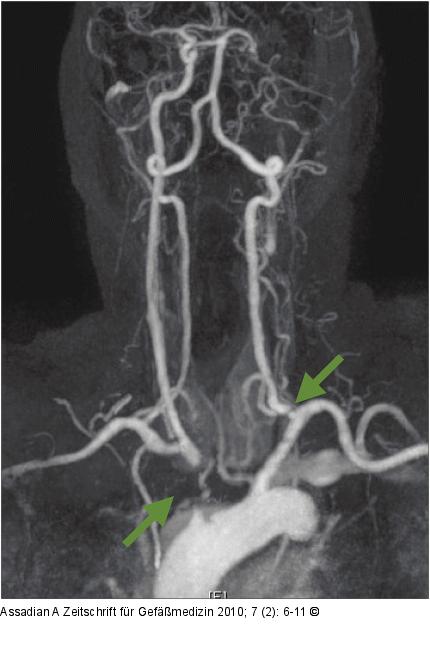

Abbildung 1: MR-Angiographie Präoperative MR-Angiographie: Verschluss des Truncus brachiocephalicus (grüner Pfeil) und der linken Art. carotis communis und interna, hochgradige Abgangsstenose der linken Art. vertebralis (grüner Pfeil). |

Präoperative MR-Angiographie: Verschluss des Truncus brachiocephalicus (grüner Pfeil) und der linken Art. carotis communis und interna, hochgradige Abgangsstenose der linken Art. vertebralis (grüner Pfeil). |